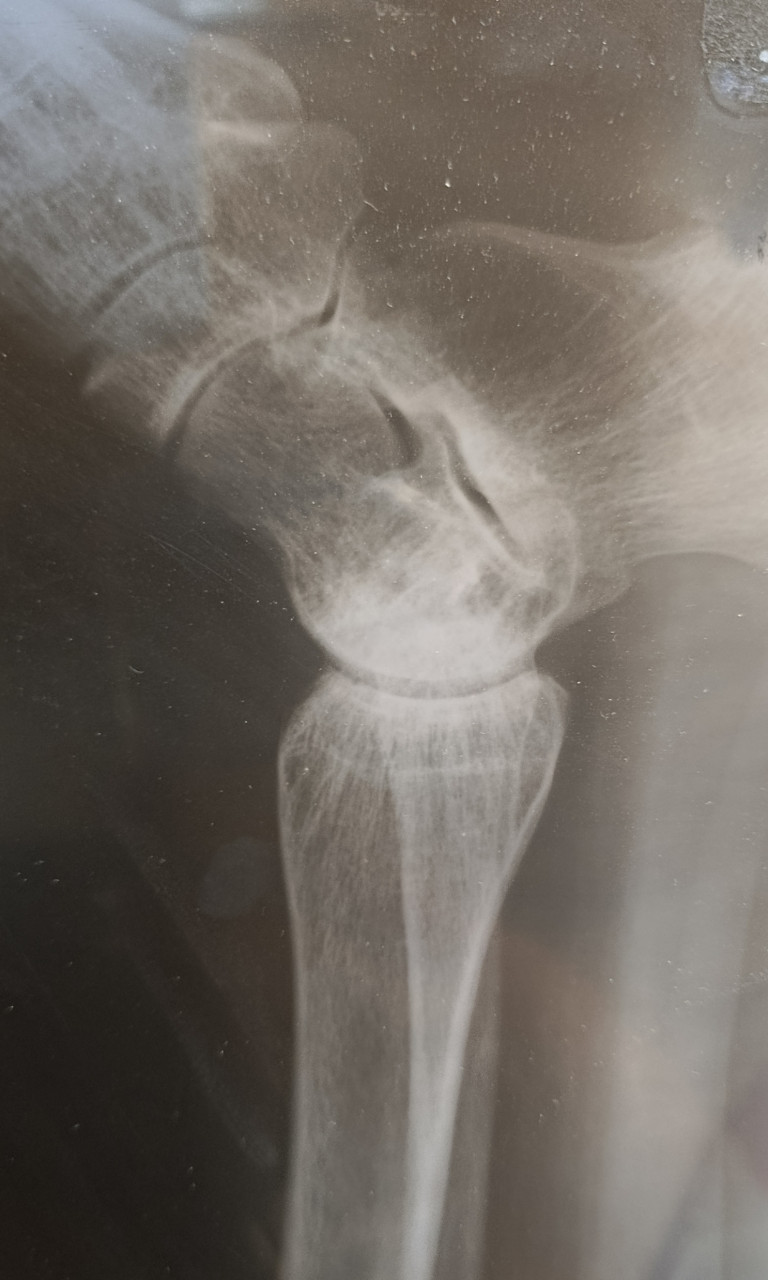

Здравствуйте. Добавила более ясное фото.. Такой снимок на рентгене. У меня перелом, а вот чего именно врач не сказал. Кости или самой лодыжки? Наложили гипс, но он очень стал давить. Пришла на прием к травматологу и его сняли с болью, просто ужас. И

отправили домой, вообще без ничего. Сказали купите ортез и носите. Оденете дома. Я на костылях пропрыгала почти 2 суток в эластичном бинте. Скажите пожалуйста, снятие гипса не может повлечь за собой дальнейшее смещение и перелом именно какой части у меня? Спасибо

Здравствуйте. На снимках виден перелом в области лодыжки, предположительно дистального отдела малоберцовой кости. Снимок с красным пятном не информативен для оценки. Снятие гипса при нестабильных переломах может привести к смещению, поэтому ортез нужно носить постоянно, а контрольный рентген обязателен. Рекомендую как можно скорее повторно обратиться к травматологу для уточнения стабильности перелома и правильной фиксации.